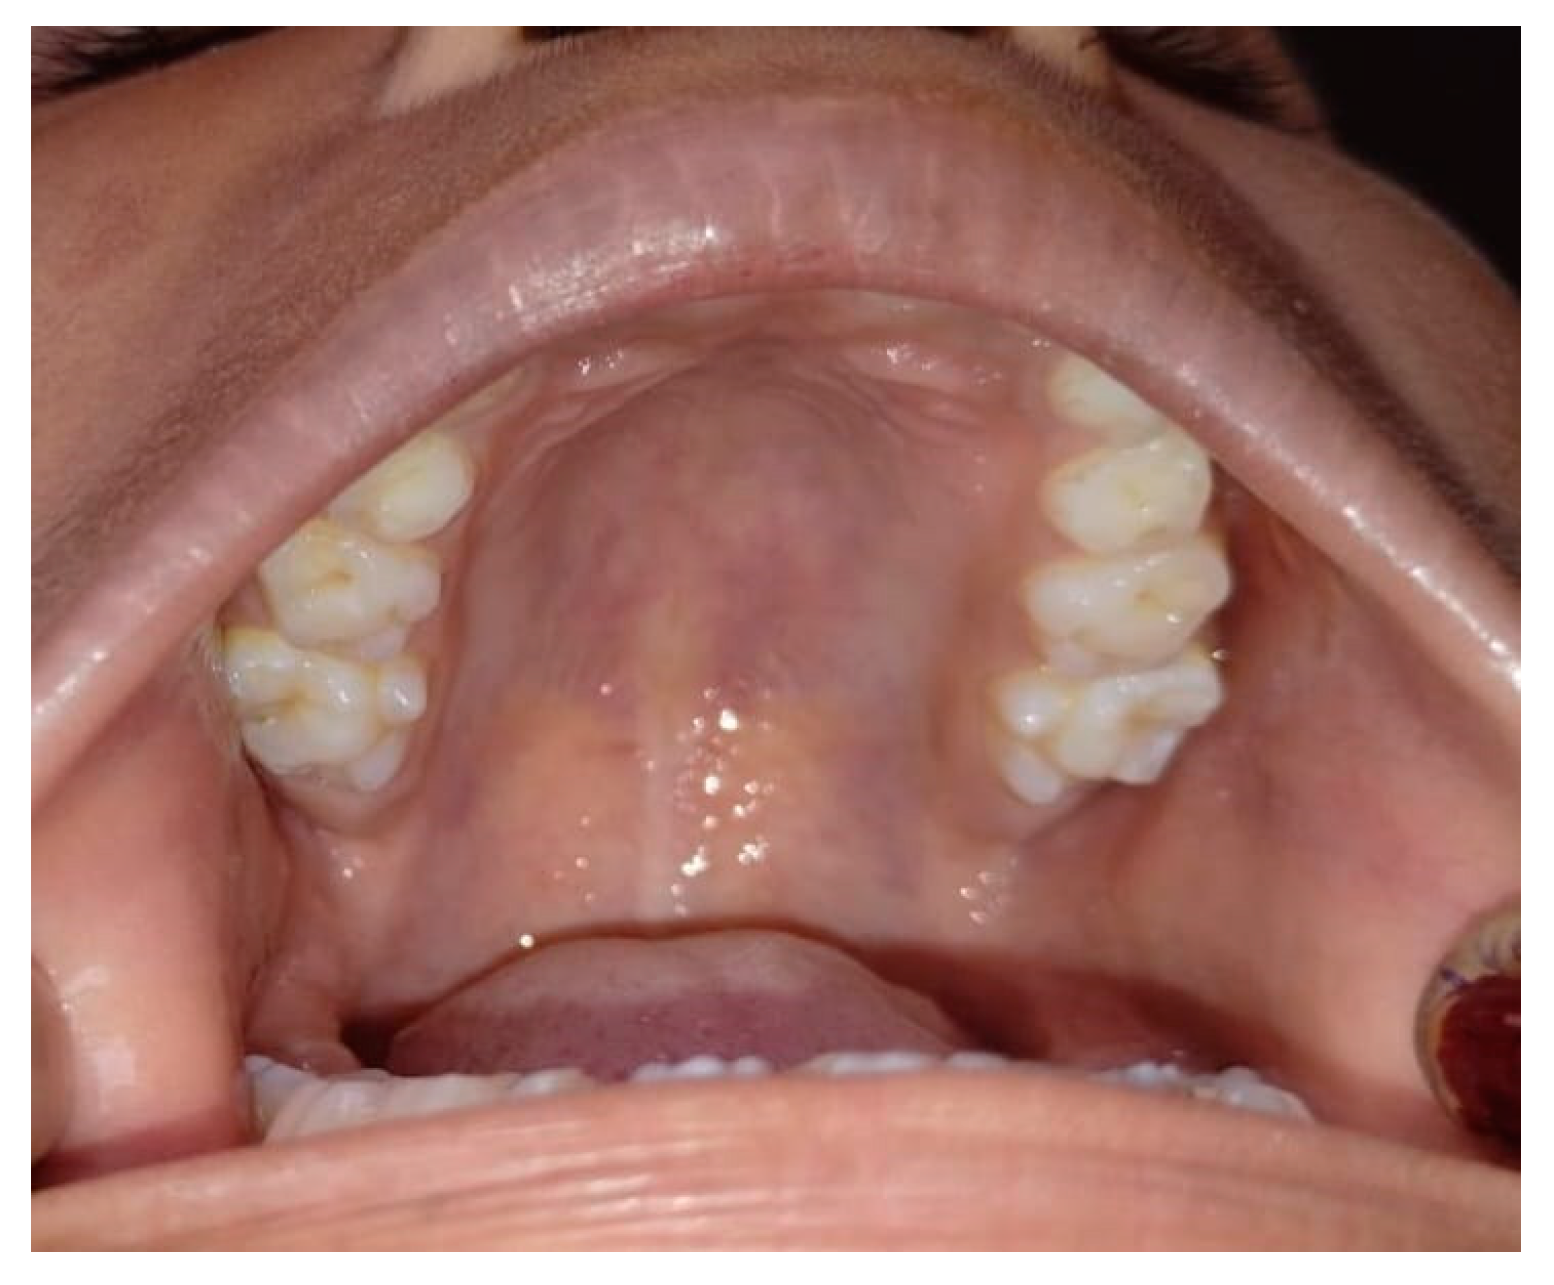

Bilateral Tuberculum Sextum of Maxillary Permanent First Molar

Deshkar, M.P.; Naik, Y.; Yeluri, R.; Thosar, N.; Khubchandani, M.; Pande, M. Bilateral Tuberculum Sextum of Maxillary Permanent First Molar. Diagnostics 2025, 15, 134. https://doi.org/10.3390/diagnostics15020134